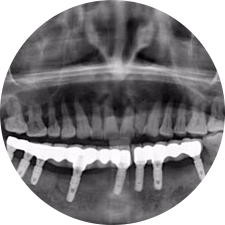

口腔種植是將人工牙根通過(guò)手術(shù)植入牙骨內(nèi),獲得牙槽骨牢固的支持,通過(guò)特殊的裝置和方式連接牙修復(fù)體,獲得與天然牙功能、結(jié)構(gòu)以及美觀相似的效果。

術(shù)前患者CBCT口掃1:1三維重建,模擬手術(shù)過(guò)程及預(yù)測(cè)術(shù)后治療效果,確定每顆植體植入的適合的種植位點(diǎn)、深度及角度,有效避免損傷頜骨重要解剖結(jié)構(gòu),提高手術(shù)準(zhǔn)確度與安全性。

Noble口腔種植體系基本不受年齡限制,適用于缺牙修復(fù),也適用于牙槽骨萎縮、骨質(zhì)疏松、高血壓、糖尿病、超高齡的患者,即種即用,只需少量微小種植體,便可輕松微痛快速重建全口咬合,特殊力學(xué)設(shè)計(jì),針對(duì)許多年紀(jì)較大,骨質(zhì)條件差,身體耐受力差的缺牙老人也能完成“即種即用”,受到廣泛好評(píng)。

惟德口腔種植體系是以患者感受為中心,取代傳統(tǒng)種植牙手術(shù)需要翻瓣、打孔、縫合,術(shù)前、術(shù)中、術(shù)后的繁復(fù)流程,采用3D導(dǎo)航微創(chuàng)準(zhǔn)確種植技術(shù),通過(guò)數(shù)字化CAD/CAM掃描技術(shù)獲得缺牙患者口腔數(shù)據(jù),以數(shù)據(jù)為基礎(chǔ)重建口腔模型進(jìn)行模擬種植。

術(shù)前將患者口內(nèi)的CBCT數(shù)據(jù)及咬合關(guān)系上傳到計(jì)算機(jī)中,建立1:1三維重建,模擬手術(shù)過(guò)程及預(yù)測(cè)術(shù)后治療效果,找出較佳種植位點(diǎn)、深度及角度,獲取實(shí)際種植體在頜骨內(nèi)的具體三維位置,有效避免損傷頜骨重要解剖結(jié)構(gòu),大大降低手術(shù)風(fēng)險(xiǎn),提升種植成功率。